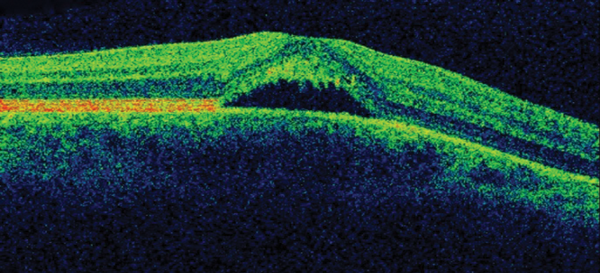

The patient was placed onto different therapeutic options during the follow-up showing no clinical response, until he underwent a definitive treatment which proved to be effective. OCT follow-up can be observed in Figure 3.

Figure 3: OCT follow-up (prior and after successful treatment).

3. There is significant evidence for different therapeutic options to be effective in CSR. First of all, observation is more than an appropriate initial approach to this disease. In addition, it is important to withdraw potential causative factors such as steroids or stress. We adopted a stepwise approach to treatment of this young patient. After a month of observation without improvement, he was commenced on low-dose aspirin for a period of four weeks. There is limited evidence for the role of aspirin in CSR, mostly originating from case series and case-control studies and it is based on its plasminogen activator inhibition effect. As there was no clinical improvement with aspirin, the patient was placed onto oral carbonic anhidrase inhibitor therapy (Acetazolamide) for a period of four weeks as a second-line therapy but did not show improvement. Both aspirin and carbonic anhydrase inhibitors may shorten clinical resolution but current evidence does not support them neither to improve final visual acuity nor to reduce recurrence rate. Three months after onset and given the persistence of both macular fluid and symptoms, the patient received photodynamic therapy (PDT) carried out at half-fluence (25mj) covering the area of choroidal hyperpermeability on ICG. The anatomical result of such is shown in OCT in Figure 3. In addition, the patient reported a complete resolution of his ocular symptoms. He remains stable after four months of PDT.